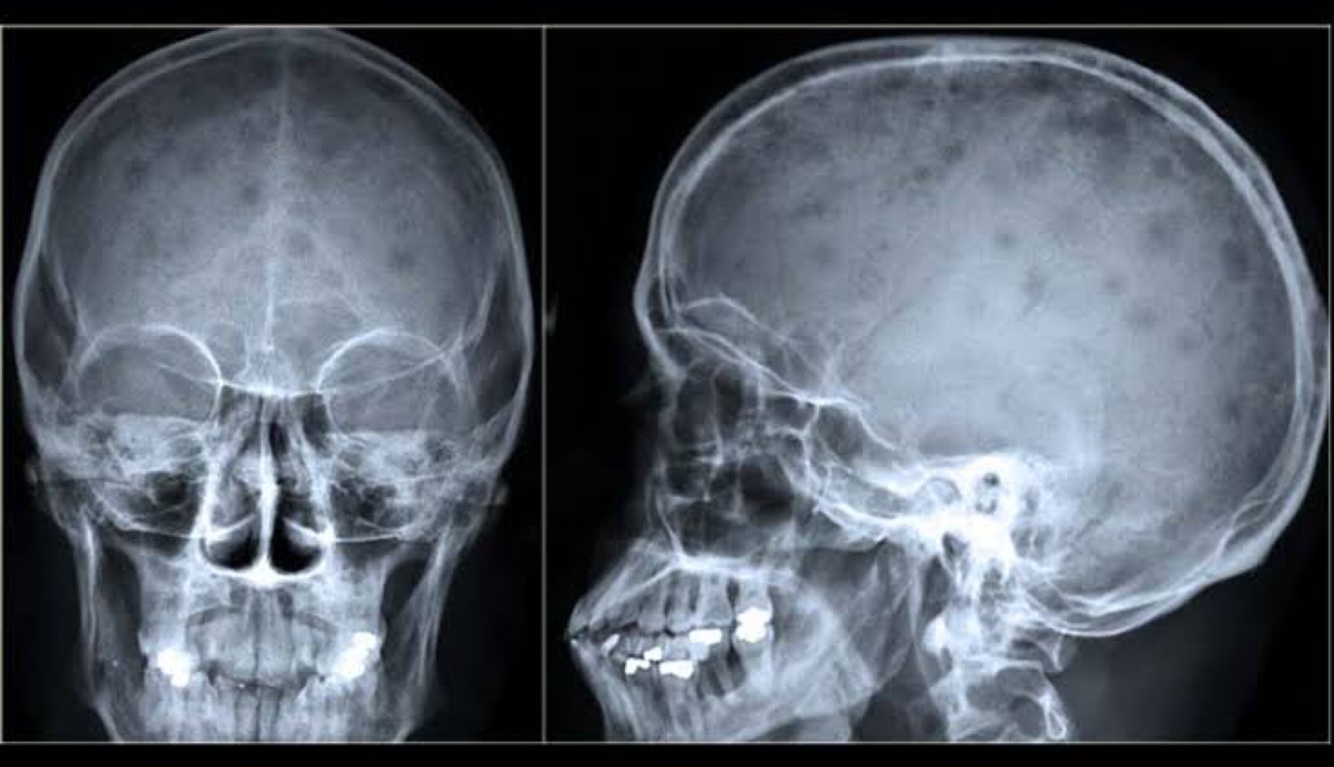

Oq é doença de HAND-SCHULLER CHRISTIAN?

A

Síndrome com Crianças e jovens( associada a langerhans )

Defeitos osteolíticos nos ossos membranosos,

Exoftalmia

Diabete insípido

A doença não costuma ser fatal> CRISTO